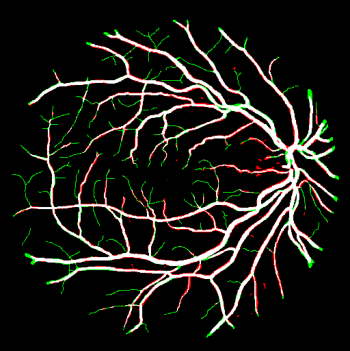

Vessel segmentation is an essential task in many clinical applications. Although supervised methods have achieved state-of-art performance, acquiring expert annotation is laborious and mostly limited for two-dimensional datasets with a small sample size. On the contrary, unsupervised methods rely on handcrafted features to detect tube-like structures such as vessels. However, those methods require complex pipelines involving several hyper-parameters and design choices rendering the procedure sensitive, dataset-specific, and not generalizable. We propose a self-supervised method with a limited number of hyper-parameters that is generalizable across modalities. Our method uses tube-like structure properties, such as connectivity, profile consistency, and bifurcation, to introduce inductive bias into a learning algorithm. To model those properties, we generate a vector field that we refer to as a flow. Our experiments on various public datasets in 2D and 3D show that our method performs better than unsupervised methods while learning useful transferable features from unlabeled data. Unlike generic self-supervised methods, the learned features learn vessel-relevant features that are transferable for supervised approaches, which is essential when the number of annotated data is limited.